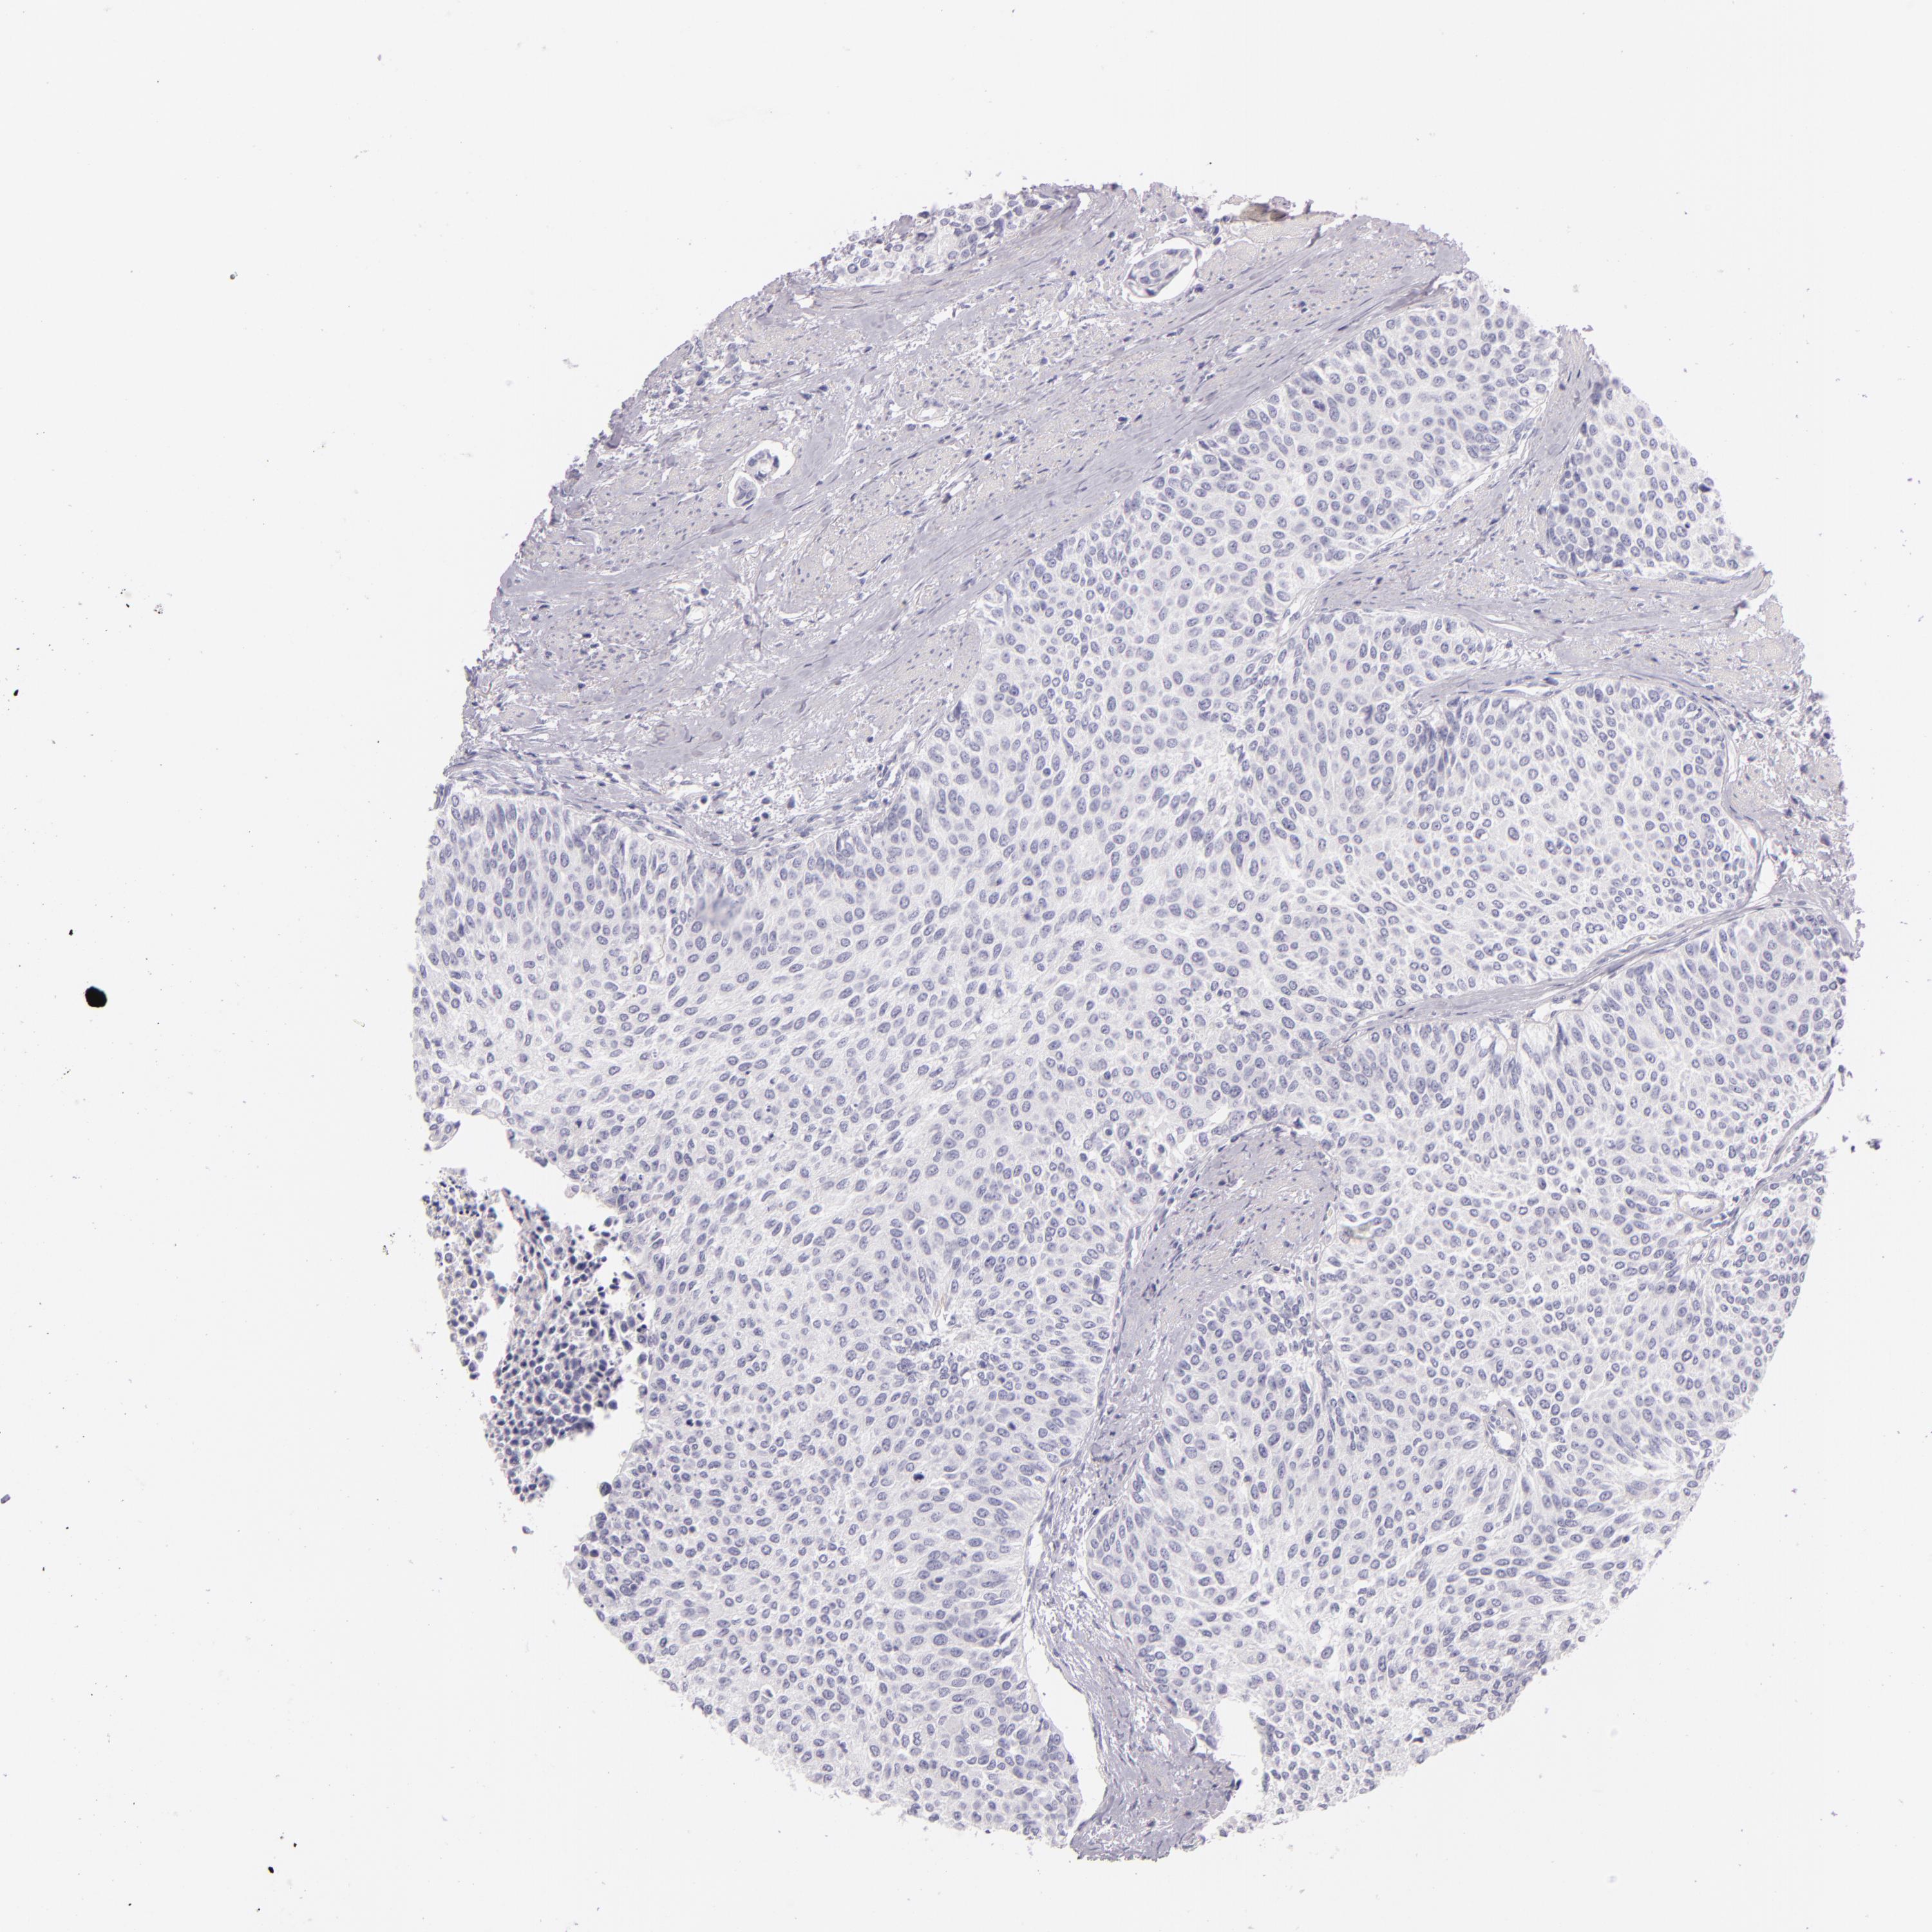

UROTHELIAL CANCER - Protein expressioni

A mouse-over function shows sample information and annotation data. Click on an image to view it in a full screen mode. Samples can be filtered based on level of antibody staining by selecting one or several of the following categories: high, medium, low and not detected. The assay and annotation is described here.

Antibody stainingi

Antibody staining in the annotated cell types in the current human tissue is reported as not detected, low, medium, or high, based on conventional immunohistochemistry profiling in selected tissues. This score is based on the combination of the staining intensity and fraction of stained cells.

Each image is clickable and will lead to virtual microscopy that enables deeper exploration of all samples and also displays staining intensity scores, fraction scores and subcellular localization as well as patient and tissue information for each sample.

Antibody HPA008057

Antibody CAB002059

Urothelial carcinoma, High grade

Urothelial carcinoma, Low grade

Adenocarcinoma, NOS